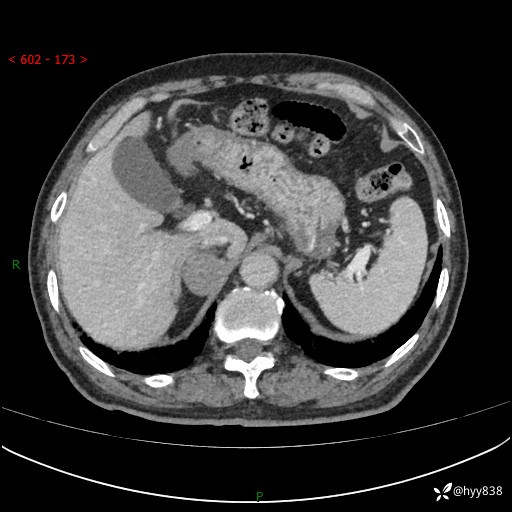

【患者信息】:76岁/男

【主诉】:检查发现右侧肾上腺占位6天

【现病史及既往史】:患者6天前体检发现右侧肾上腺占位,无腰痛,无放射痛,无尿频、尿急、尿痛及肉眼血尿,无畏寒、发热,无恶心、呕吐,今为求进一步治疗,遂来我院就诊,门诊拟“右侧肾上腺占位”收住入院。 起病以来,患者精神、饮食、睡眠可,大小便如常,体力体重无明显变化。

【检查】:肾上腺CT平扫+增强